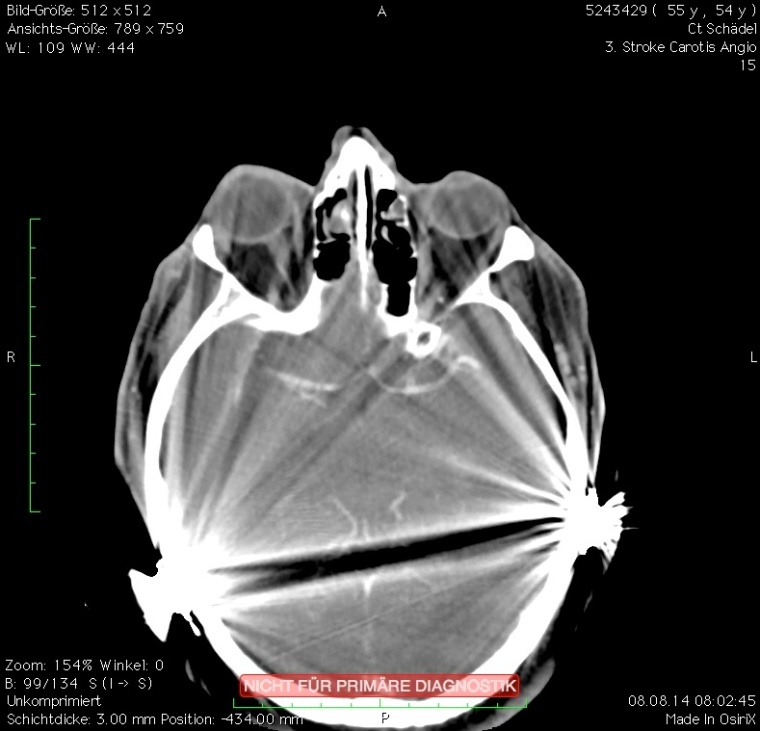

Erschwerend hat der Patient beidseitige Cochlea-Implantate (CI), so dass zum einen ausgeprägte Aufhärtungsartefakte die Diagnostik erschweren (Bild 2 a) und zum anderen eine alternative MRT-Untersuchung nicht möglich ist. In der anschließenden CT-Angiografie, als Spiral-CT gefahren, erschweren die Aufhärtungsartefakte eine genaue Lokalisation des Gefäßverschlusses (CTA Bild 2 b). In dem anschließend sekundär berechneten CTA-Datensatz (Bild 2 c) zeigt sich ein eindeutig zu diagnostizierender Verschluss der rechten A. cerebri media im M2-Segment als Ursache für die linksseitige Hemiparese. Die in der CTA noch ausgeprägten Aufhärtungsartefakte werden nach der SEMAR-Rekonstruktion deutlich reduziert, so dass hieraus auf vergleichbaren Schnittebenen ein klarer diagnostischer Zugewinn resultiert (Vergleich Bild 2 b und Bild 2 c). Zusätzlich kann in diagnostischer Qualität eine Ganzhirnperfusion errechnet werden, so dass die Frage nach einem Perfusionsmismatch ebenfalls beantwortet werden kann.